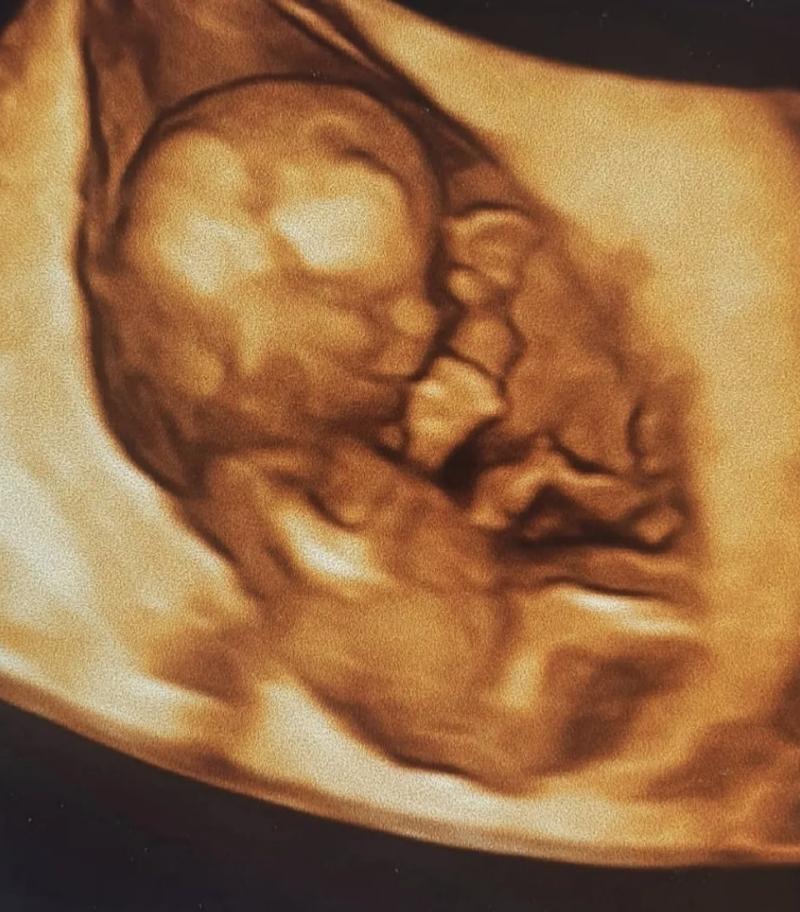

Recientemente a través de sus redes sociales reveló que está esperando su primer hijo junto a su esposo, el ingeniero comercial José Schmitz, con quien se casó en octubre del año pasado.

“Estamos tan felices que te integres a la familia. Eres de lo más lindo que nos ha pasado y de las noticias más hermosas y mágicas que hemos tenido que dar con tu papá”, inició su relato.

En esa línea, agregó, “te cuidaremos y te daremos todo el amor que imagines del mundo para que seas tremendamente feliz y libre mi amor. @jose.sch”, concluyó la hija de Carlos Pinto, junto a tres registros fotográficos entre ellos una imagen de la ecografía que confirmaba su embarazo.

Mira los imágenes publicadas por la hija de Carlos Pinto: